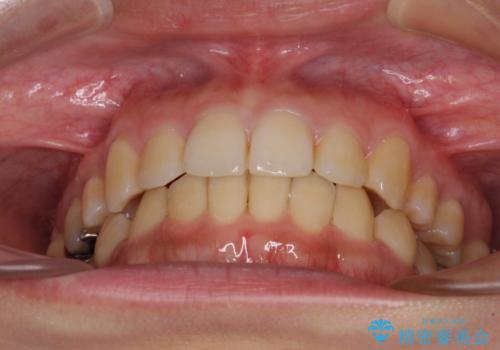

八重歯の抜歯矯正 補助装置を用いたインビザライン矯正

装着時間をしっかりと守ってくださったので、予定通りの期間で終了することができました。